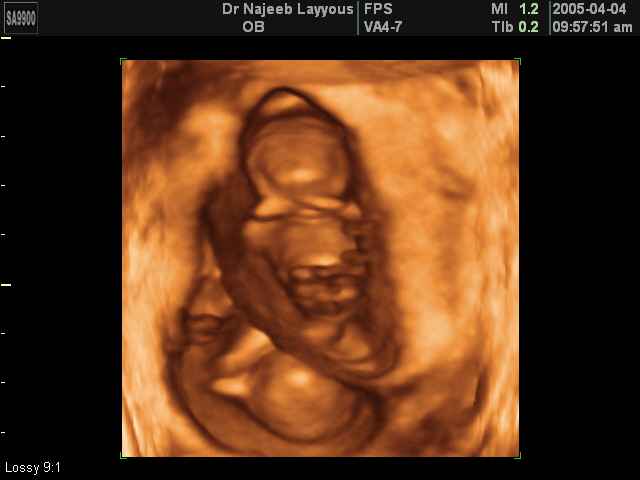

- لقطات فيديو للجنين بجهاز الموجات فوق صوتية رباعي الأبعاد

- صور لوجه الجنين في داخل الرحم

- صور جانبية لرأس الجنين

- صور لأعضاء الجنين

- صور لأطراف الجنين

- صور للجنين في المراحل الأولى من الحمل

- صور لتصرفات الجنين داخل الرحم

- صور لتوائم

- صور للجنين في المراحل المتوسطة من الحمل

صور لتوائم بجهاز الالتراساوند ثلاثي الأبعاد | الدكتور نجيب ليوس